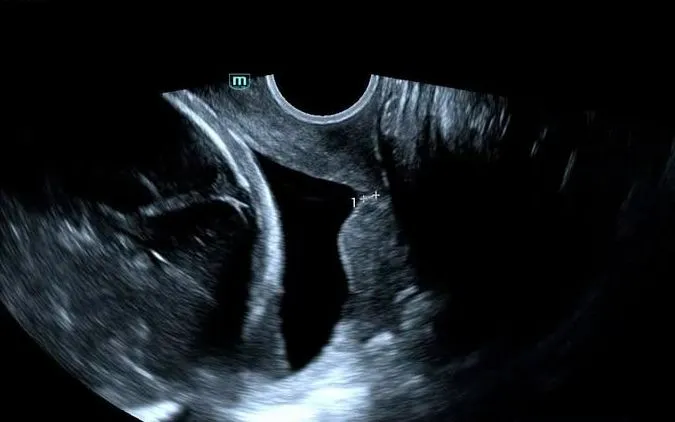

Sản phụ 26 tuổi nhập Bệnh viện Sản Nhi Nghệ An trong tình trạng nguy kịch khi cổ tử cung phía mang thai rút ngắn chỉ còn 2mm, không đủ giữ túi ối. Với dị dạng hai cổ tử cung, nguy cơ sinh non tăng cao, thai kỳ đứng trước nguy cơ chấm dứt sớm.

Trước tình huống khẩn cấp, các bác sĩ đã hội chẩn và quyết định thực hiện khâu vòng cổ tử cung. Đây là thủ thuật khó, đòi hỏi xác định chính xác vị trí can thiệp trên nền giải phẫu bất thường, nhằm tránh vỡ ối hoặc kích thích chuyển dạ.

Theo các bác sĩ, dị dạng hai cổ tử cung là yếu tố nguy cơ cao gây hở eo tử cung và sinh non. Việc phát hiện sớm qua siêu âm và can thiệp kịp thời có ý nghĩa quyết định trong việc giữ thai.